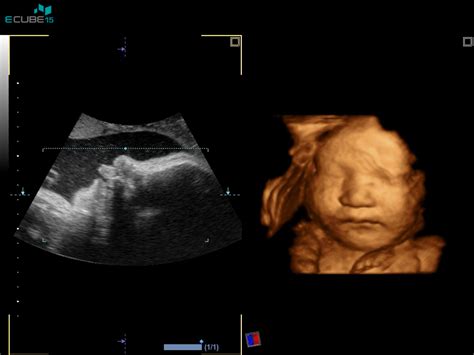

Za spremljanje količine plodovnice se uporabljajo različne metode, med katerimi je najpogostejši ultrazvočni pregled. Z ultrazvokom se lahko oceni globina najglobljega žepa plodovnice (DP) ali izračuna indeks plodovnice (AFI), ki predstavlja seštevek globine štirih žepov v vseh kvadrantih maternice. Kot normalne vrednosti AFI veljajo med 8 in 18 centimetri, medtem ko se vrednosti med 8 in 12 cm pogosto štejejo za blag hidramnij, od 12 do 15 cm za zmeren, nad 15 cm pa za hud hidramnij.